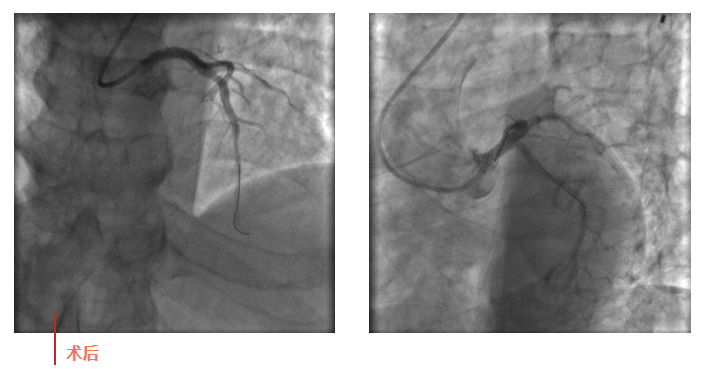

心血管內(nèi)科副主任徐先進(jìn)在主任助理農(nóng)彥林和主任汪念東的配合下行冠狀動(dòng)脈造影,結(jié)果如術(shù)前判斷一致,左主干重度狹窄,患者命懸一線。對(duì)團(tuán)隊(duì)緊急處置非常信任的李阿姨,毫無(wú)疑慮地聽取了術(shù)者的建議,同意在血管內(nèi)超聲(IVUS)的精準(zhǔn)指導(dǎo)下,在患者左主干內(nèi)植入一枚支架,成功拯救了患者的生命。

術(shù)后,患者轉(zhuǎn)入心血管內(nèi)科CCU病房,在IABP泵的支持下渡過(guò)了危險(xiǎn)期。李阿姨紅著眼眶坐在床邊,仍心有余悸,“還好有你們??!真是太謝謝了!”經(jīng)過(guò)心血管內(nèi)科團(tuán)隊(duì)的精心治療和護(hù)理,患者現(xiàn)已康復(fù)出院。